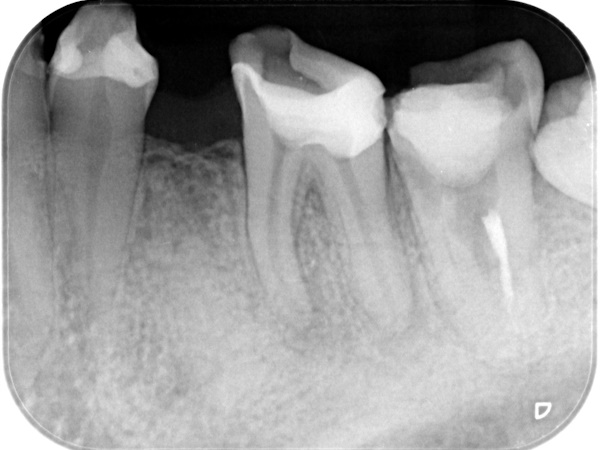

【 下の歯の精密根管治療 】

治療前と治療後の比較

術前から術後までの治療の流れ

初診時

根管治療中(試適時)

根管治療終了時

根管治療終了後3か月経過